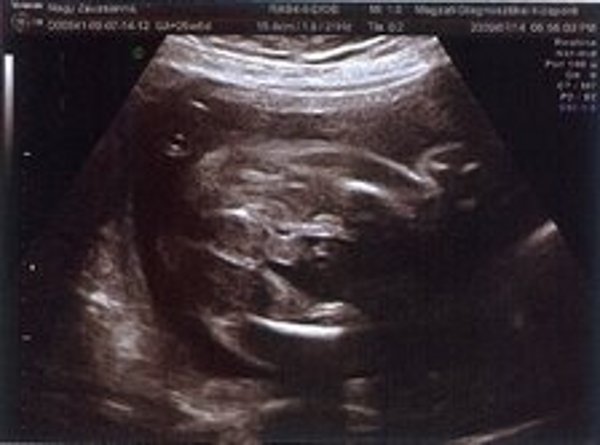

Nézzétek a kukim:

Kép

Zsuzska

Milyen édes kis arcocskája van :)

Édes kis turcsi orra lesz, mint apukájának van.... anyum szerint tiszta apja :lol: :lol: :lol: :lol: :lol: :lol: :lol: :lol:

Jajj de szép Benőke! :) És tényleg látszik a kis kukija. :) Jajj meg azok a csöpp kis lábacskák! :) Na és a kis pofija... :) Megvallom könny szökik a szemembe... Hogy mennyire várom már, hogy láthassam a teljes valójában! :) GOndolom te még jobban.:)

Leírhatatlan érzés volt látni ilyen formában is. Anyum szerint már most tiszta apja a gyerek :lol: :lol: :lol: :lol: :lol: :lol: :lol: :lol:

A doki ott mosolygott végig. De marhára nem tetszett, amikor beszólt nekem, hogy eléggé vaskos a hasfalam :evil: :evil: :evil: :evil: :evil: :evil: Én is majdnem mondtam neki valamit... de hát anyu előtt csak nem :? :? :? :? :? :?